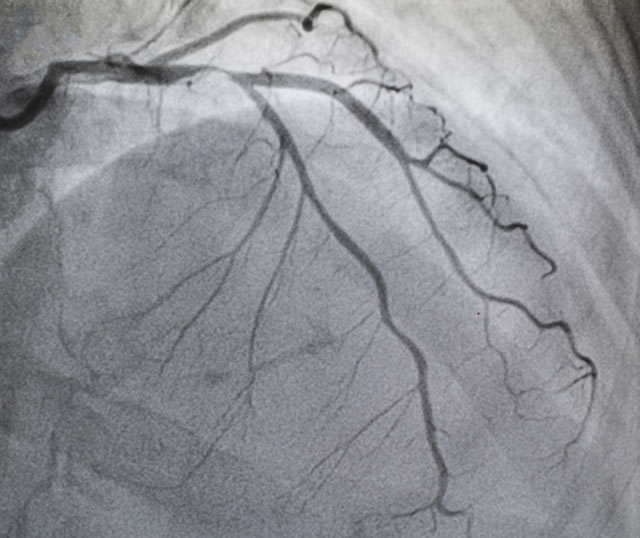

The field of cardiology is complex since it covers different areas. Cardiomyopathy is the altered mechanical function of the muscle of the heart e.g. weakening or stiffening of the heart muscle found in heart failure. Coronary artery disease causes a narrowing of the blood vessels that supply blood to the heart, which may lead to angina or a heart attack. Dysrhythmias (also known as arrhythmias) are abnormal heartbeats and can sometimes be life-threatening. Other areas include congenital (from birth) or inherited (genetically passed from one generation to another) heart problems, as well as conditions affecting the valves inside the heart.